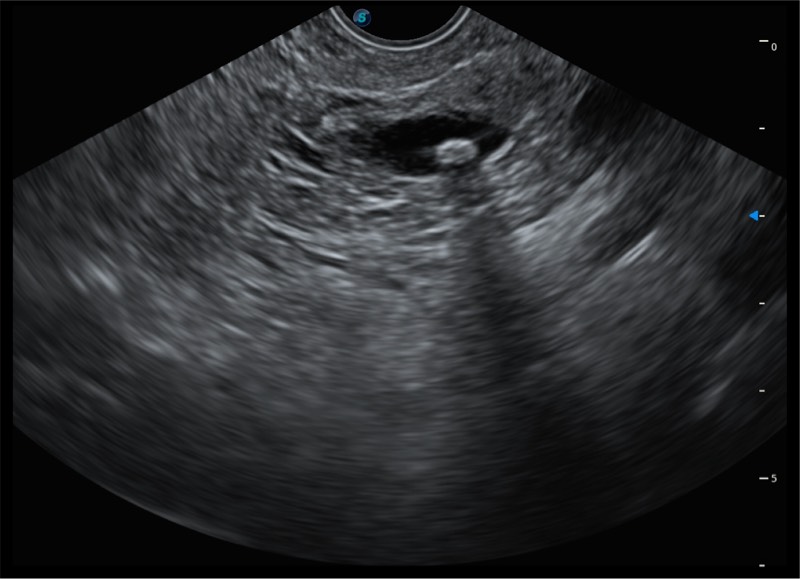

基于二十年的超声技术积累,狗万官方网站提供了最新一代的独立超声主机,在提供高质量图像的同时满足多学科使用。具备常见多普勒技术并提供弹性成像、声学造影等高端影像技术。新一代传感器具有更强的抗干扰能力并减少图像伪影。

150°超声扫描角度